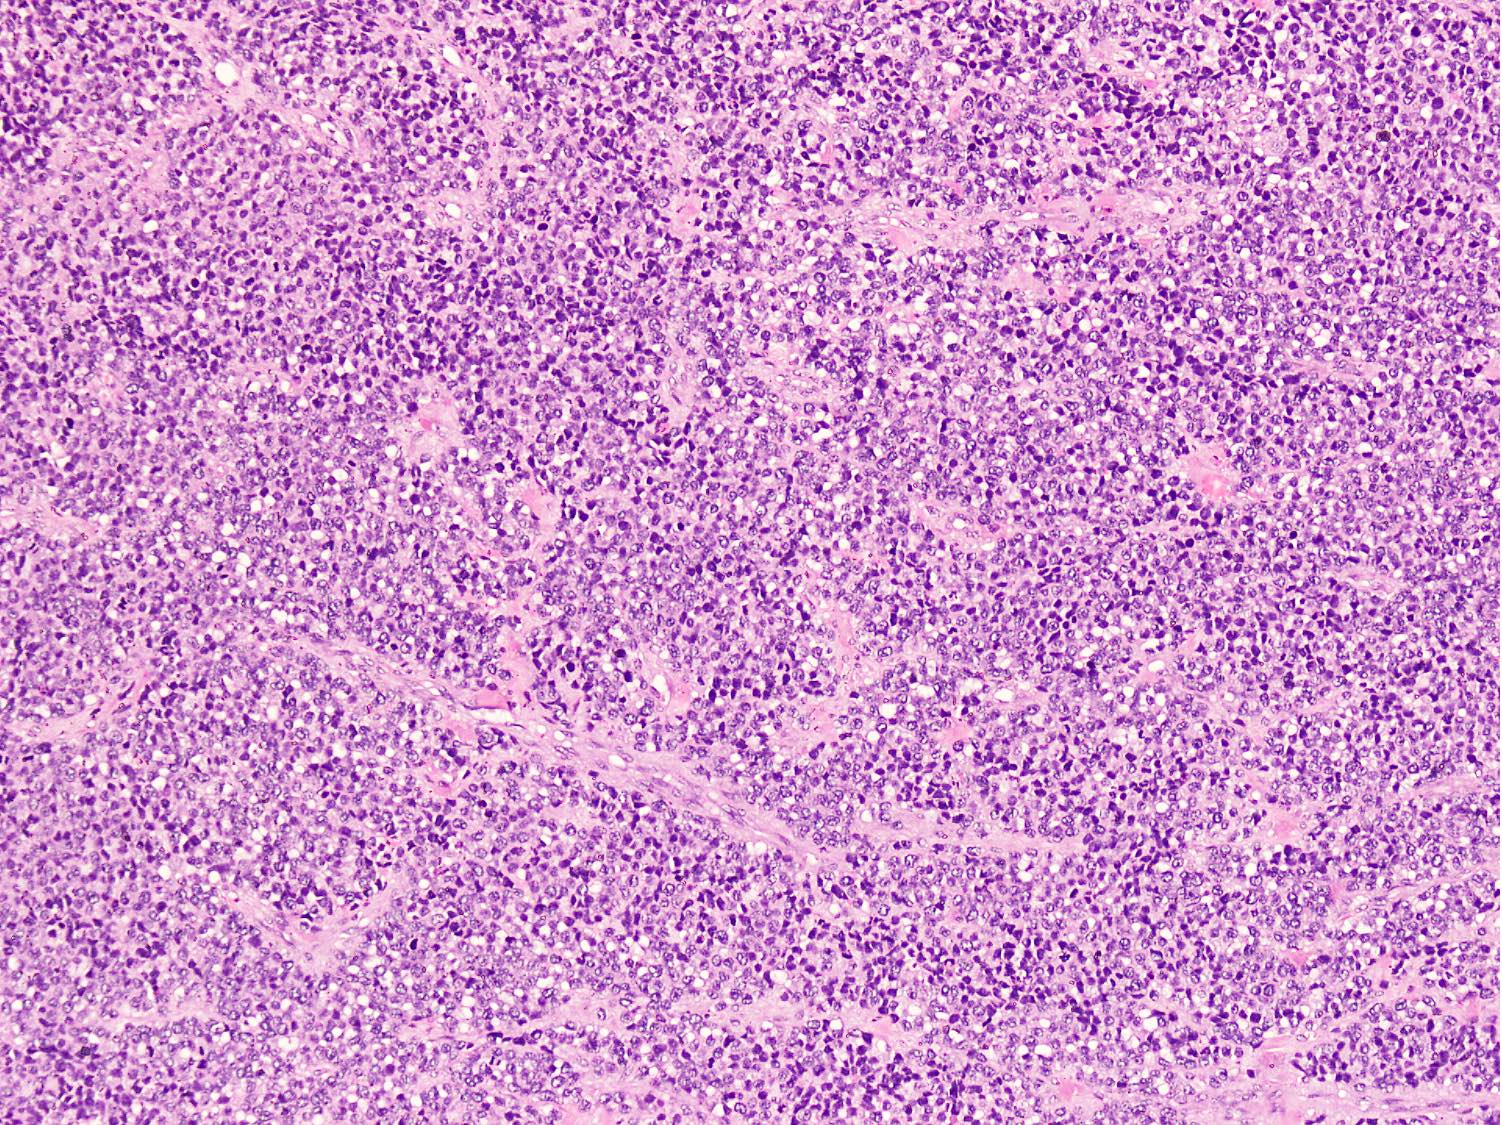

Microscopic (histologic) description

- Cellular round cell tumor

- Large clusters, nests, cords and trabeculae of primitive round cells, separated by variably thick fibrovascular septa

- Loss of cellular cohesion in the center forms alveolar-like, cystic and vague papillary appearance (Histopathology 2022;80:98)

- Layer of cells adheres to the periphery of the spaces and fibrous septa

- Small to intermediate sized monomorphic cells with scant cytoplasm

- Hyperchromatic nuclei with variable conspicuous small nucleoli

- Cells in the center have poor preservation and are necrotic; may appear floating

- Multinucleated tumor giant cells with wreath-like lineup of nuclei are common (Acta Pathol Microbiol Immunol Scand A 1982;90:345)

- Round to oval rhabdomyoblasts with abundant acidophilic cytoplasm may be present

- Brisk mitosis and variable tumor necrosis

- Occasional cases may show clear cell morphology with pale, glycogenated cytoplasm

- Rare anaplasia

- Some cases may show histologic features of embryonal rhabdomyosarcoma; molecular studies are essential to characterize such cases (Am J Clin Pathol 2013;140:82)

- Solid variant:

- Sheets of neoplastic cells

- Lack fibrovascular septa, pseudoalveolar spaces and dyscohesion (Cancer Genet Cytogenet 2005;163:138)

- May show rhabdomyoblastic differentiation

- Abundant mitotic activity

Microscopic (histologic) images

Contributed by Nasir Ud Din, M.B.B.S.